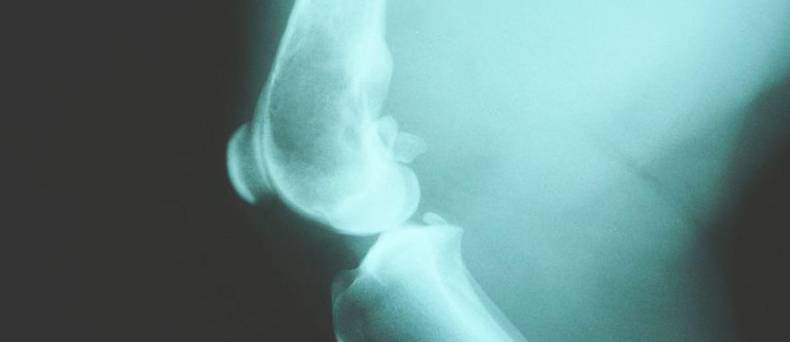

Door middel van radiografie wordt de diagnose gesteld.

Vaak zal de hond een roesje krijgen voor dit onderzoek. Hij wordt dan op de rug gelegd en de poten worden loodrecht naar achter getrokken. Dit is pijnlijk. Naar aanleiding van de ernst die waargenomen wordt zal een beoordeling worden gegeven van A tot D aan alle twee de heupgewrichten. Hierbij is  A het beste resultaat is. Rashonden die voor de fok worden gebruikt moeten beoordeeld worden door de keuringscommissie. Ze mogen alleen gebruikt worden voor de fok als ze voldoen aan de vereisten.Bron foto: Joel Mills